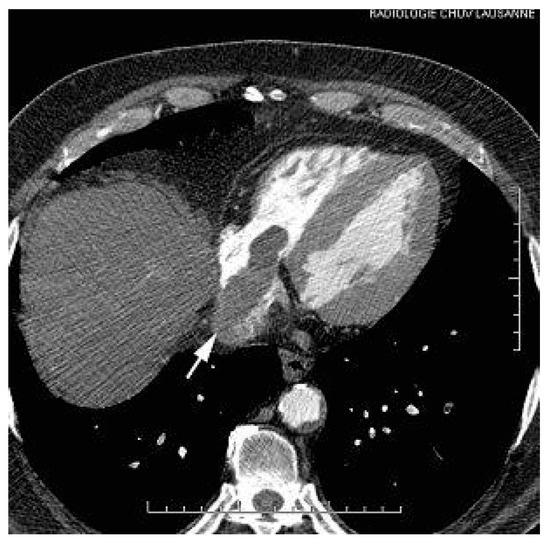

This report describes a case of involvement of inferior vena cava and the right atrium (RA) by a hepatocellular carcinoma (HCC), incidentally discovered during a transthoracic echocardiography in a patient with segmental left ventricular dysfunction,...